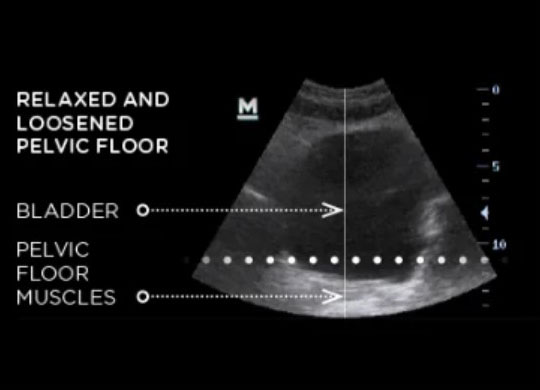

Emsella is a revolutionary, non-invasive treatment that helps strengthen the pelvic floor muscles to address urinary incontinence and improve intimate well-being. This FDA-cleared device uses High-Intensity Focused Electromagnetic (HIFEM) technology to induce thousands of supramaximal pelvic floor muscle contractions in a single session.

During an Emsella treatment, you simply sit on the specially designed chair, fully clothed, while it stimulates the entire pelvic floor region. One 28-minute session is equivalent to performing 11,200 Kegel exercises, providing a comprehensive workout for your pelvic floor muscles.

Strengthens Pelvic Floor

Tones and firms pelvic muscles for better support